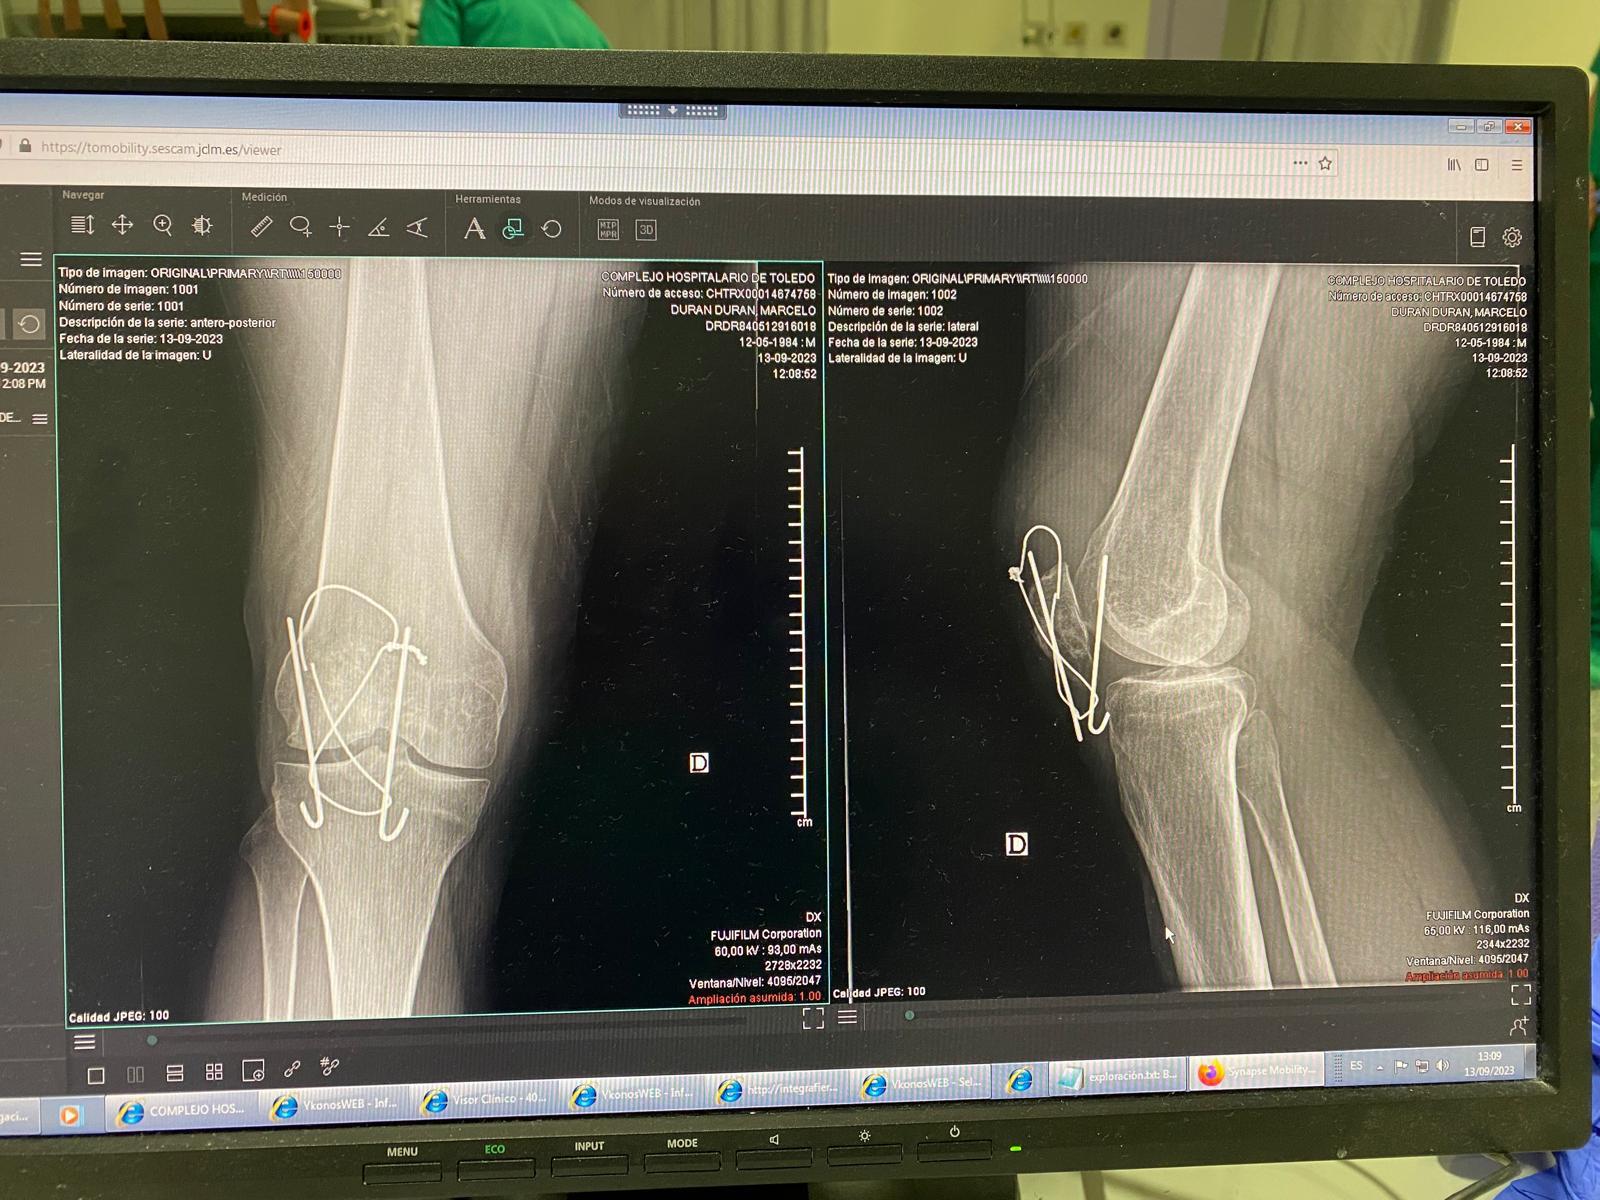

Dolor de rodilla derecha.

Juicio clínico, diagnóstico diferencial, identificación de problemas

Juicio clínico: Hemartros en contexto de rotura de material de osteosíntesis.

Evolución

Paciente se cita en AP a los 30 días de la extracción de material de osteosíntesis, en la exploración física se objetiva herida quirúrgica limpia sin signos de infección, movilidad activa y pasiva de la rodilla recuperada totalmente con algún grado de dolor EVA 3/10 a últimos grados de movimientos en flexo-extensión, no signos de flogosis ni complicaciones postoperatorias inmediatas ni mediatas durante su estancia hospitalaria.